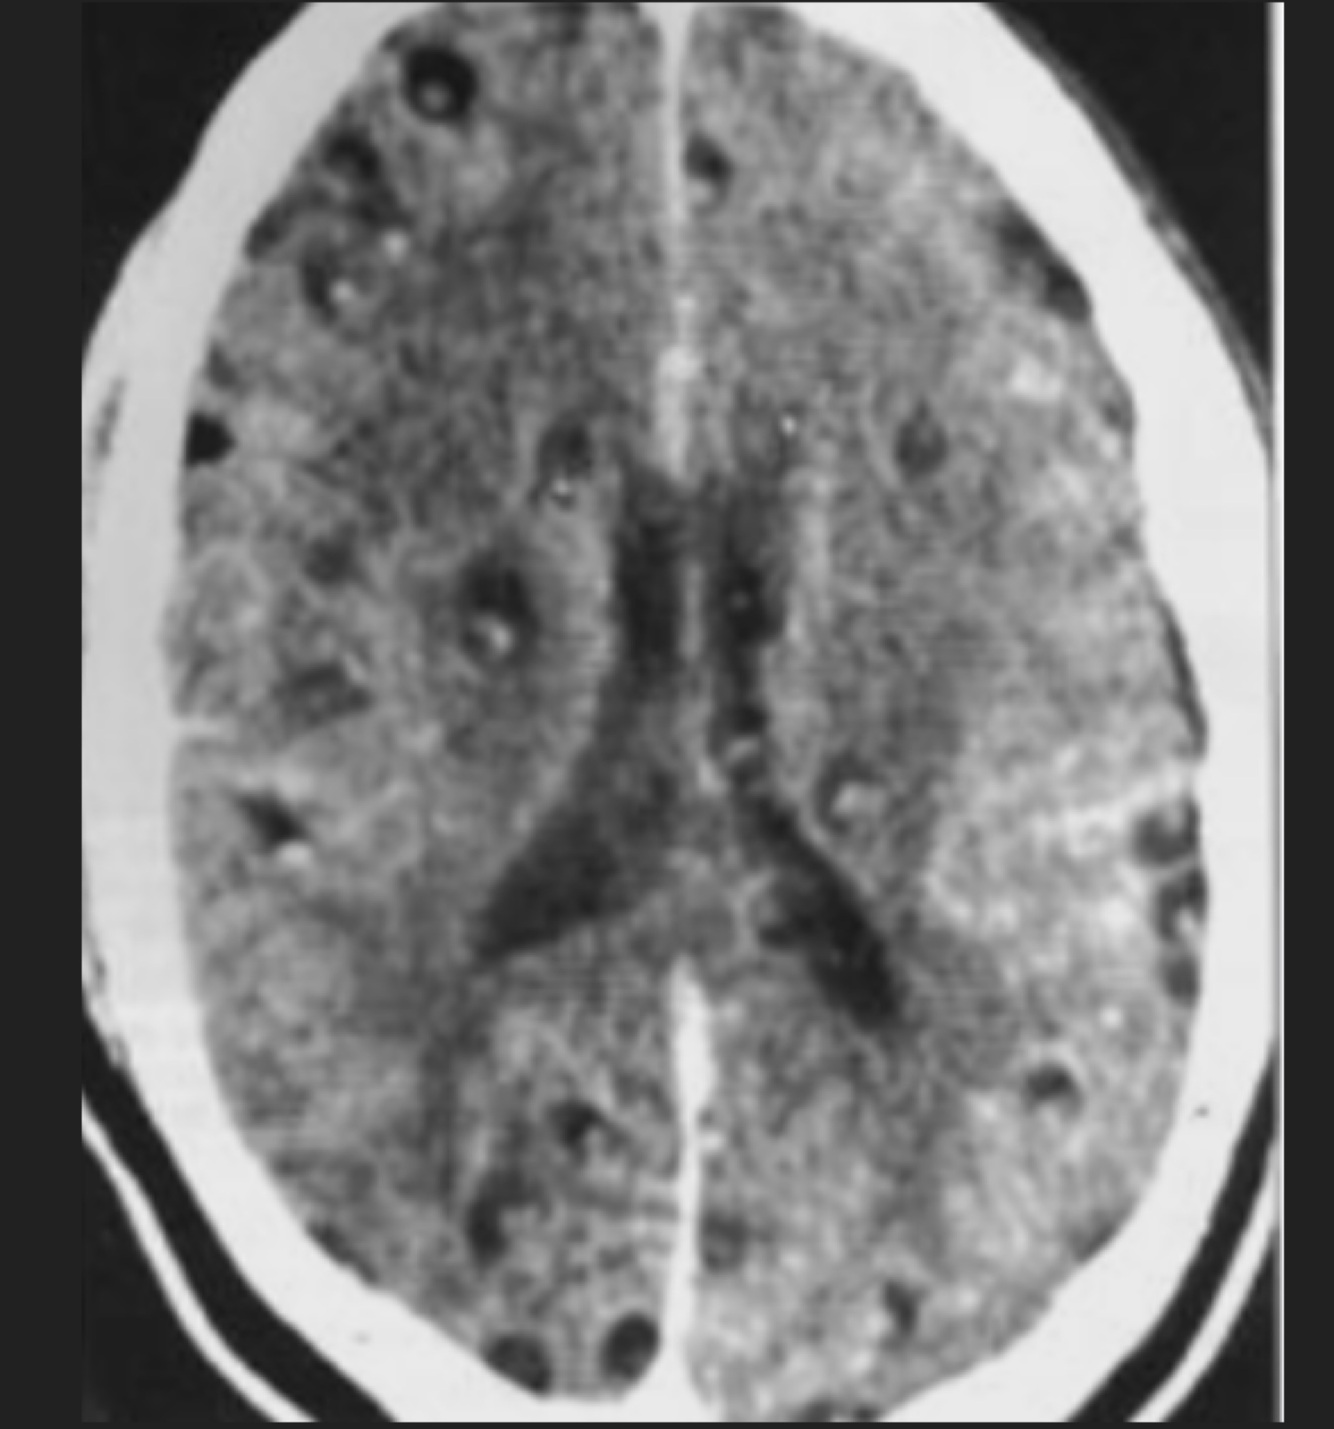

Q

Femenino de 72 años de edad, con cefalea y crisis convulsivas

A

Neurocisticercosis